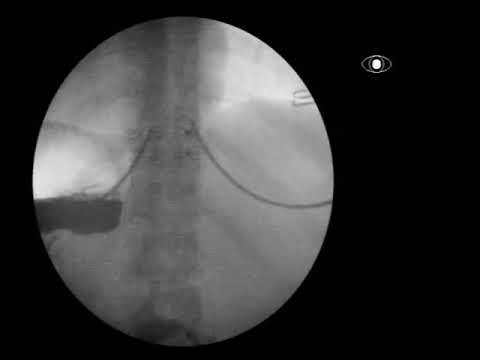

Эндоскопия при ахалазии пищевода: что нужно знать